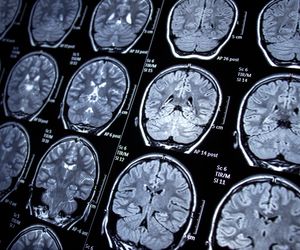

Neurologia zajmuje się diagnostyką i leczeniem chorób obwodowego i ośrodkowego układu nerwowego. W Polsce neurologię dzieli się na dwie specjalizacje – klasyczną oraz dziecięcą. Do przykładowych jednostek chorobowych na tym tle zalicza się m.in. zapalenie mózgu, chorobę Alzheimera, czy zmiany nowotoworowe jak glejaki lub oponiaki. Nieleczone schorzenia na tle neurologicznym nie tylko znacząco obniżają komfort życia. Mogą także doprowadzić do utraty znacznej części możliwości poznawczych, a nawet śmierci pacjenta.